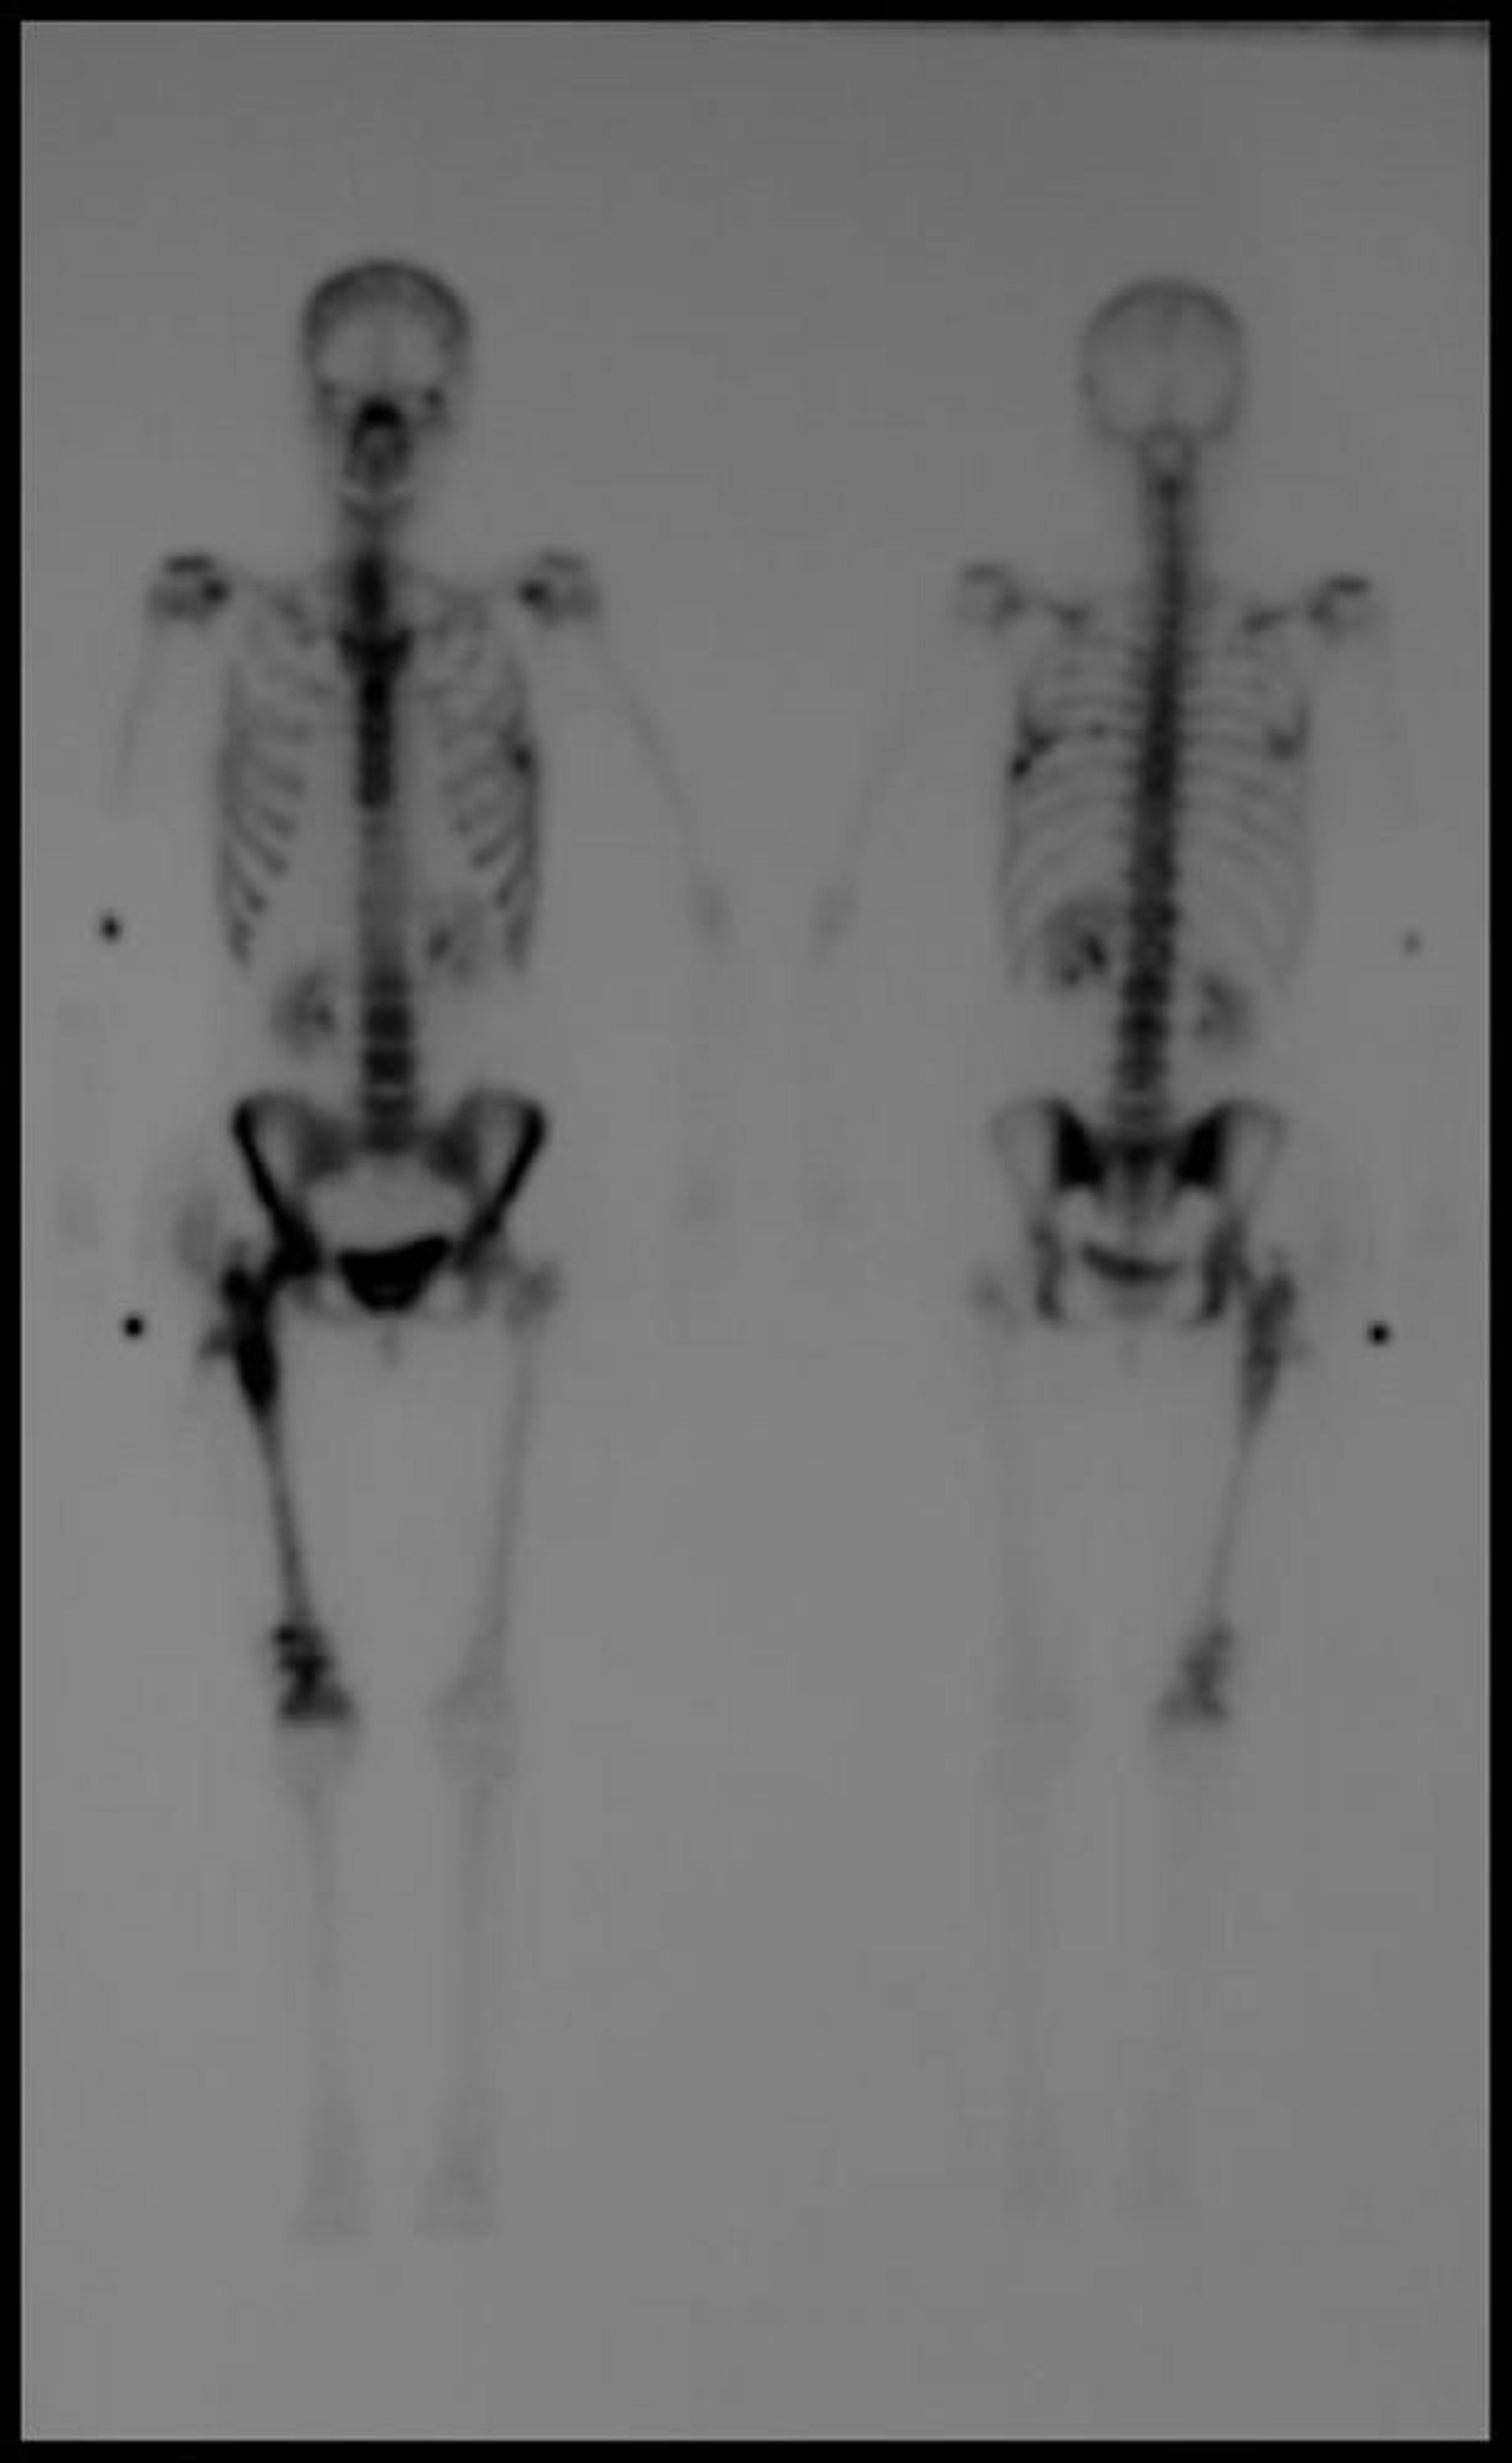

Centellografía ósea del cuerpo entero

La imagen retrasada con tecnecio-99m de la centellografía ósea de todo el cuerpo muestra múltiples focos de aumento de captación compatible con patología metastásica.